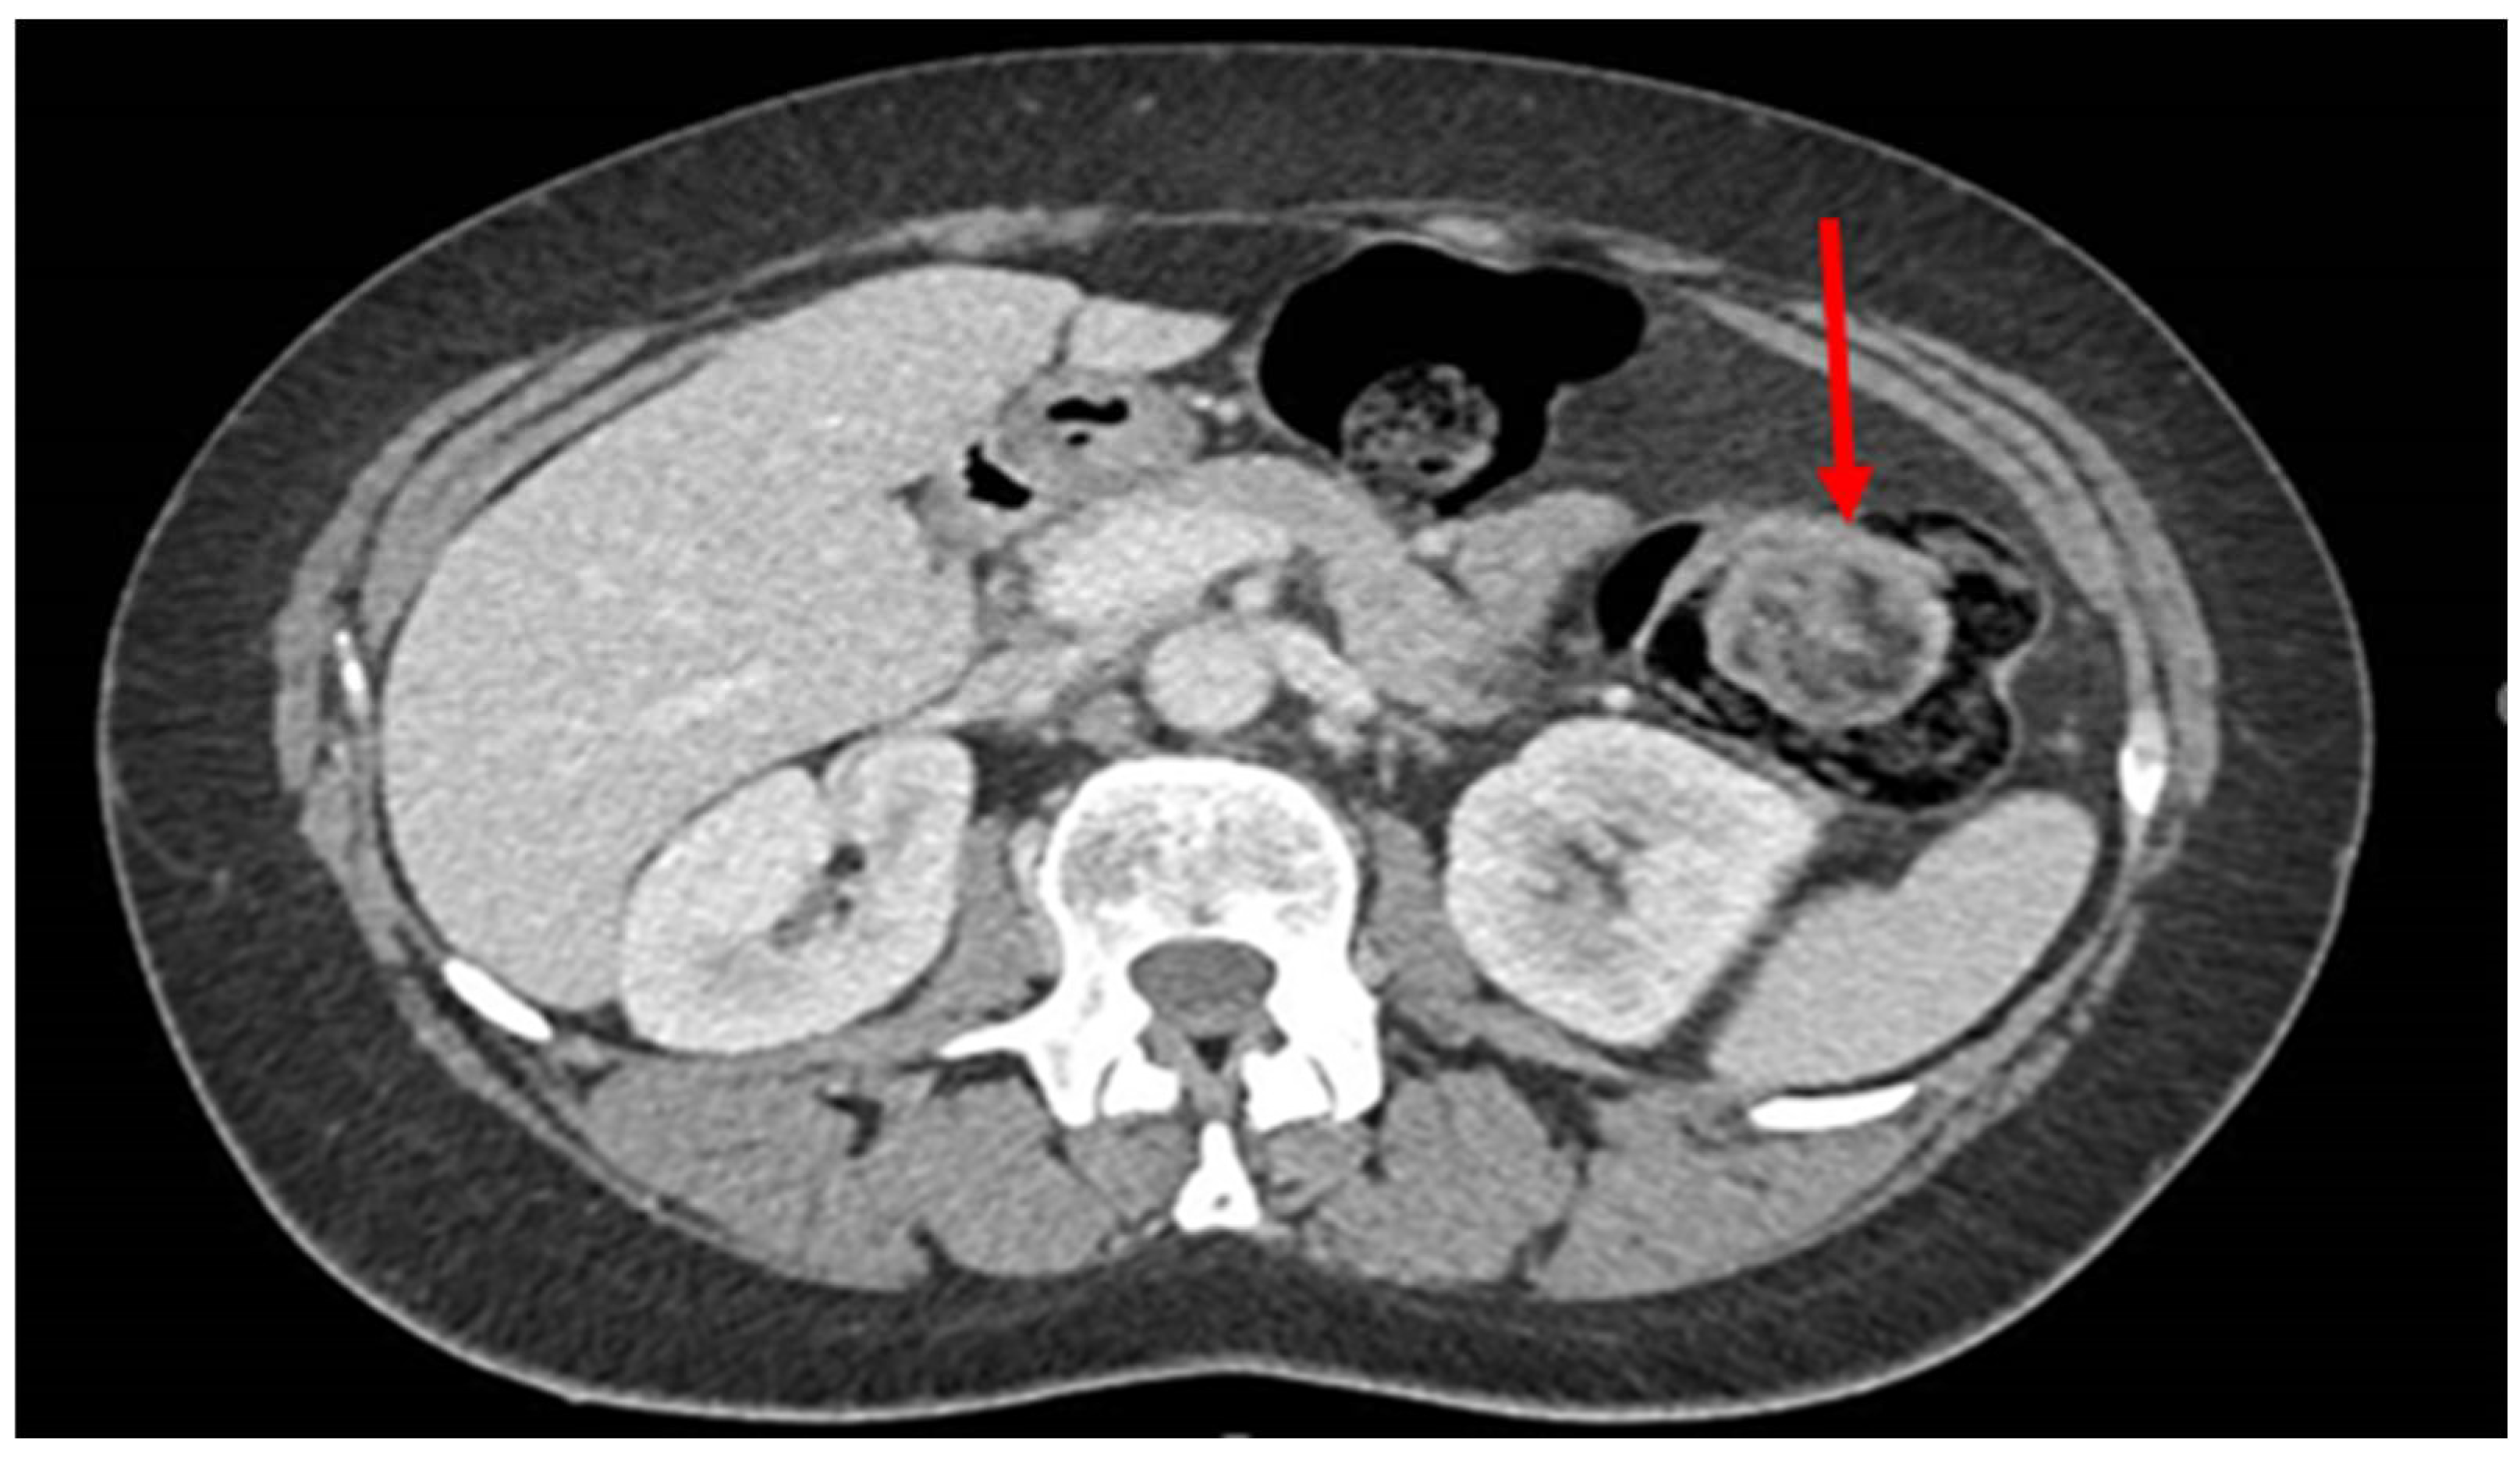

- 7 cases in which the lipoma was presumably associated with symptoms including abdominal pain, hematochezia, and even intussusception. In 3 of these cases, we had a pre-treatment diagnosis as the symptoms required the execution of pre-endoscopic radiological examinations.

| Case 6 | M | 61 | TC-RMN-colonoscopy | 5 cm | sigma | Surgical | 0 |